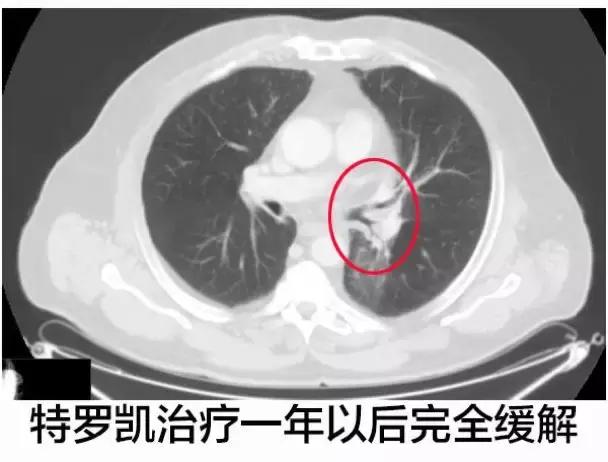

在最后一次CT影像学扫描,左肺下叶导致呼吸困难的区域还能辨识的出来,但是实体肿瘤几乎不见了,特罗凯治疗1年之后达到了完全的缓解。